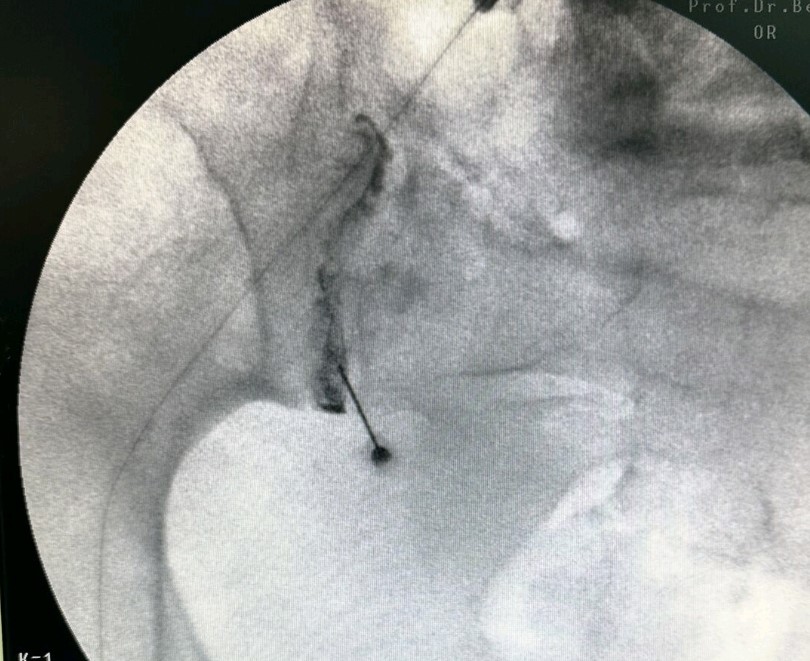

Τι είναι η έγχυση και η απονεύρωση της ιερολαγόνιου άρθρωσης

Η έγχυση αφορά στη χορήγηση διαλύματος τοπικού αναισθητικού και κορτιζόνης απευθείας στο κατώτερο τμήμα της ιερολαγονίου άρθρωσης υπό ακτινοσκοπική καθοδήγηση. Η απονεύρωση γίνεται με χρήση θερμοπηξίας ή κρυοπηξίας και στοχεύει στην κατάλυση των αισθητικών κλάδων που τροφοδοτούν την ιερολαγόνιο άρθρωση, οι οποίοι βρίσκονται παραπλεύρως κάθε ιερού τρήματος.